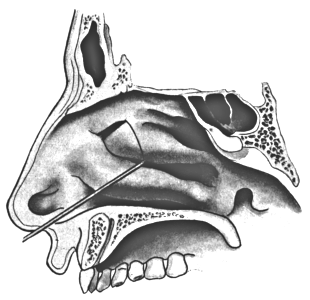

| 320. | Catheterizing the Maxillary Sinus | 626 |

| 333. | Catheterizing the Frontal Sinus | 639 |